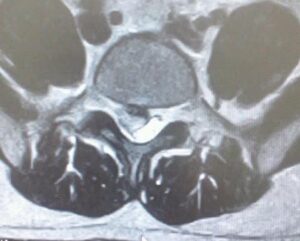

私自身の以前の腰のMRIです。白いのが神経で黒い部分がヘルニアで巨大な脱出型ヘルニアです。